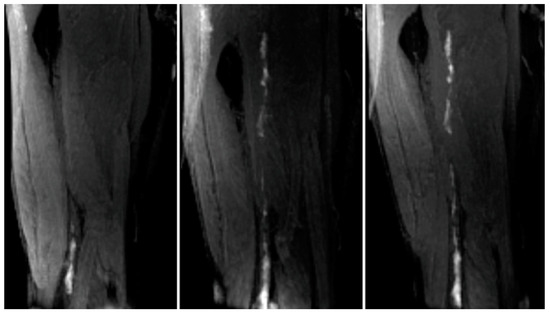

- Moody, A.R. Direct imaging of deep-vein thrombosis with magnetic resonance imaging. Lancet 1997, 350, 1073. [Google Scholar] [CrossRef]

- Saha, P.; Andia, M.E.; Modarai, B.; Blume, U.; Humphries, J.; Patel, A.S.; Phinikaridou, A.; Evans, C.E.; Mattock, K.; Grover, S.P.; et al. Magnetic Resonance T 1Relaxation Time of Venous Thrombus Is Determined by Iron Processing and Predicts Susceptibility to Lysis. Circulation 2013, 128, 729–736. [Google Scholar] [CrossRef]

- Phinikaridou, A.; Andia, M.E.; Saha, P.; Modarai, B.; Smith, A.; Botnar, R.M. In vivo magnetization transfer and diffusion-weighted magnetic resonance imaging detects thrombus composition in a mouse model of deep vein thrombosis. Circ. Cardiovasc. Imaging 2013, 6, 433–440. [Google Scholar] [CrossRef]

- Wu, G.; Morelli, J.; Xiong, Y.; Liu, X.; Li, X. Diffusion weighted cardiovascular magnetic resonance imaging for discriminating acute from non-acute deep venous Thrombus. J. Cardiovasc. Magn. Reson. 2019, 21, 667. [Google Scholar] [CrossRef]

- Chen, H.; He, X.; Xie, G.; Liang, J.; Ye, Y.; Deng, W.; He, Z.; Liu, D.; Li, D.; Liu, X.; et al. Cardiovascular magnetic resonance black-blood thrombus imaging for the diagnosis of acute deep vein thrombosis at 1.5 Tesla. J. Cardiovasc. Magn. Reson. 2018, 20, 1556. [Google Scholar] [CrossRef]